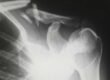

Frattura di spalla nello sport. Negli ultimi anni abbiamo assistito ad un grande infortunio di un motociclista famosissimo del Moto GP. Rotolando fuori pista, è stato colpito dalla moto al braccio destro che le ha provocato una frattura diafisaria trasversale all’omero destro.

L’intervento è stato eseguito per risolvere la pseudoartrosi dell’omero destro. Questa condizione si presenta quando i due monconi dell’osso fratturato non riescono a saldarsi completamente.